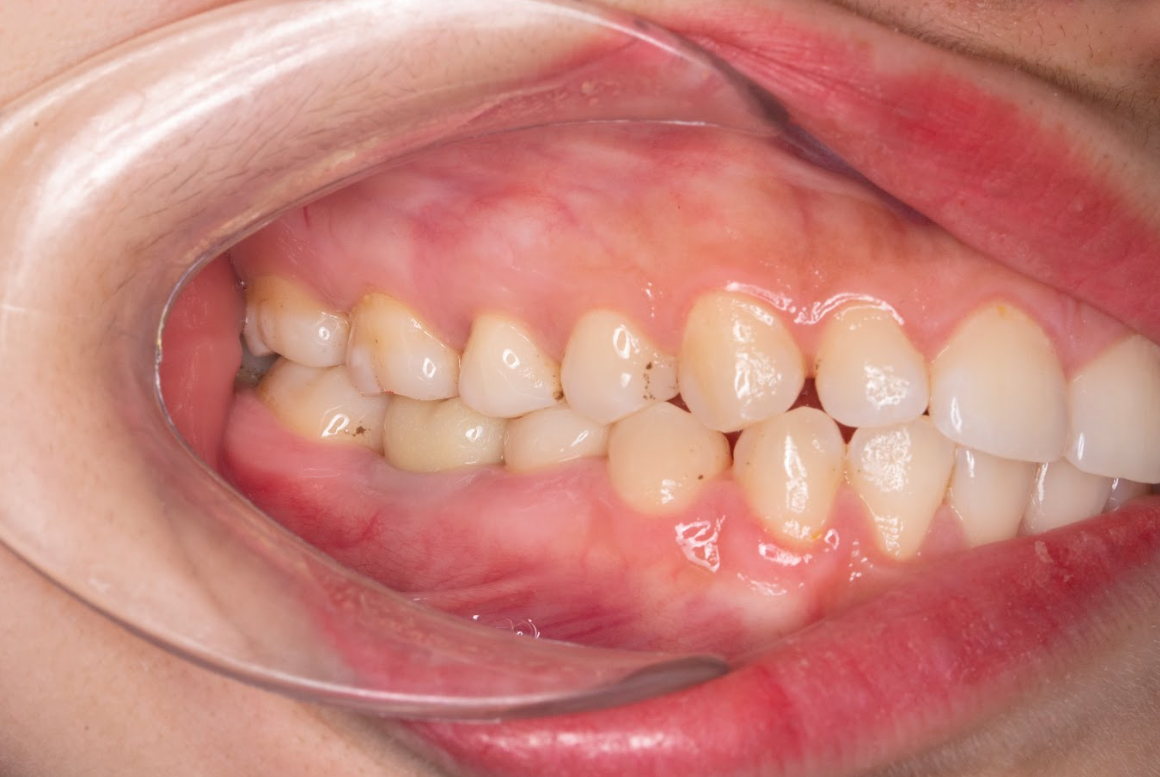

Kết quả sau khi trồng răng Implant

Khớp cắn ổn định, ăn nhai chắc chắn, thoải mái.

Không ảnh hưởng răng thật kế cận như cầu răng sứ trước đây.

Thẩm mỹ tự nhiên, nụ cười hài hòa, khó phân biệt đâu là răng Implant.

Bệnh nhân rất hài lòng: “Em thấy khác hẳn cầu răng, ăn uống chắc chắn, không còn lo sâu răng trụ. Em tiếc là không chọn Implant sớm hơn.”